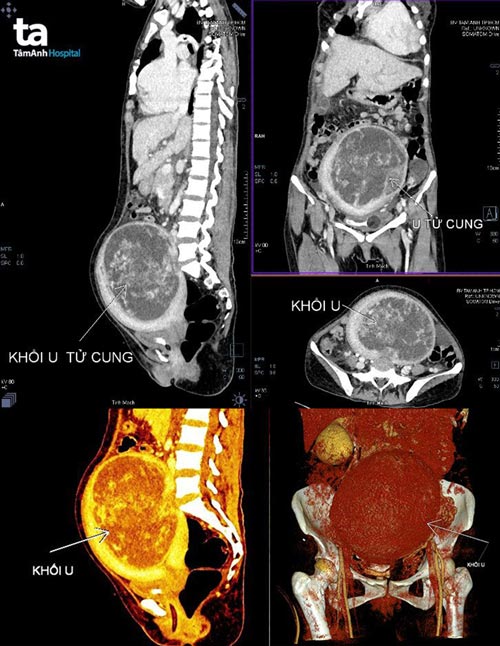

Siêu âm bụng của bệnh nhân ngay tại giường hồi sức tích cực phát hiện có khối bướu rất lớn hơn 30cm gợi ý đến u xơ tử cung, và tràn dịch đa màng. Bệnh nhân được hội chẩn liên chuyên khoa Hồi sức tích cực, Tim mạch, Sản Phụ khoa, có quyết định cần tiếp tục nâng thể trạng và thực hiện chụp cắt lớp điện toán (CT scan) ngực bụng để đánh giá thêm tình trạng bệnh sau khi bệnh nhân tạm ổn định qua cơn nguy kịch.

Bác sĩ CKI Võ Duy – Trung tâm Chẩn đoán hình ảnh chia sẻ: “Chúng tôi đã chuẩn bị sẵn sàng khi được báo có ca bệnh nhân nặng cần chụp CT Scan. Với máy CT Scan 768, quá trình chụp chỉ diễn ra chưa đến 3 phút. Khi vừa nhìn vào phim, chúng tôi bị ấn tượng mạnh vì khối u quá lớn ở vùng chậu và phát triển rất cao, vượt qua cả rốn của bệnh nhân Tuyền.

Phim cũng cho thấy khối này có thành phần mô và dịch hoại tử chiếm trọn buồng tử cung, ranh giới khá rõ, bắt thuốc tương phản mạnh sau tiêm, không thấy dấu hiệu xâm lấn mô mềm vùng chậu. Những thông tin này gợi ý chẩn đoán đây là một trường hợp u xơ tử cung ‘khổng lồ’ thoái hóa, tuy vậy chưa loại trừ hoàn toàn được bệnh lý ác tính cơ trơn tử cung (Sarcoma). Bên cạnh đó bệnh nhân còn có hình ảnh tràn dịch đa màng: trung thất, màng phổi và màng bụng”.